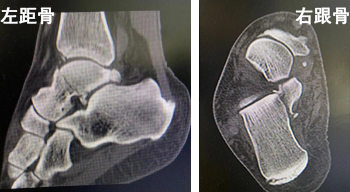

自3月28日以来,徐州市疫情形势紧张,抗疫人员肩扛重担,投身疫情防控工作中。4月8日,徐州县区一抗疫人员在工作中意外受伤,伤后即感双足跟肿痛、畸形、活动受限,在当地医院行拍片检查提示:左距骨骨折。

随后,患者来到betway在线登陆,他告诉接诊医生,右足负重行走时有疼痛感,行进一步检查显示右跟骨骨折,急诊拟“左距骨骨折、右跟骨骨折”将患者收治入院。

术前CT